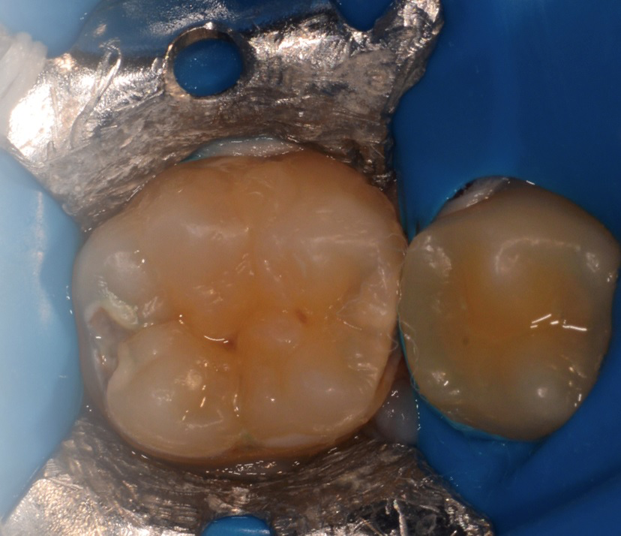

The “stamp” technique can be used in Class II cavities (Fig. 1) if the practitioner follows a two-step procedure: first reconstructing the mesial surface, and then filling the cavity as a Class I. The only restriction of the technique is to choose teeth with intact occlusal anatomy.

Fig. 1: A pre-operative photograph. Fig. 2: A stamp replicating the occlusal anatomy of the molar is made with a light cure flowable resin or hard setting liquid dam material. A bur is placed in the material to serve as a handle, and then it is light cured.